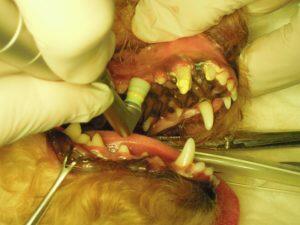

3.まず、スケーリングをして口の中をきれいにしてから

4.プロービング検査で歯周ポケットの深さを測定して